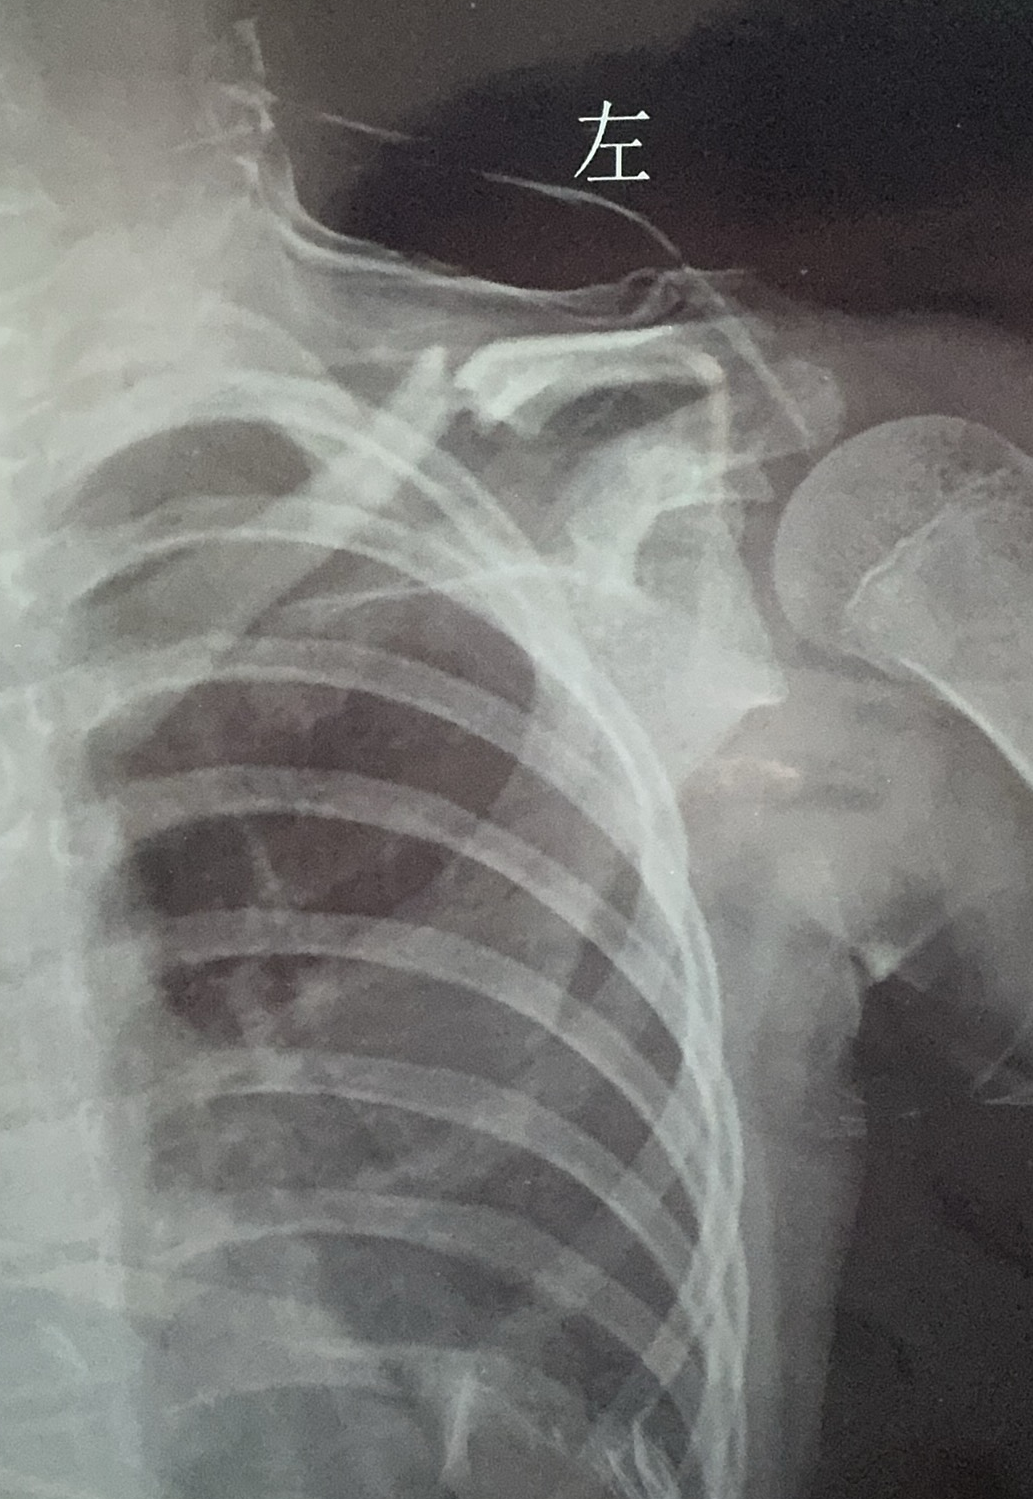

(术前X光片显示骨折明显移位)

"针对儿童患者,我们采用了特制的超细弹性髓内针。"主管医生详细解释,"这种设计能完美避开生长板,不会影响骨骼的正常发育,同时提供足够的稳定性让骨折顺利愈合。"

小雨,女,11岁,舞蹈班学员

小雨从小学习芭蕾舞,梦想成为一名专业的舞者。在一次高难度跳跃动作练习时,她不小心失去平衡,右肩着地导致锁骨骨折。